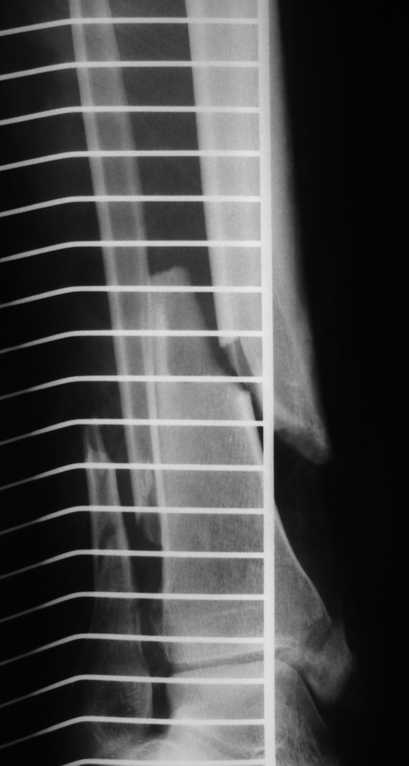

1. Ilizarov frame as definitive managment (it is crucial to perform high-quality about ankle fixation for early distal ring removing and ROM restoration) - see photo.

I've sent you picture of the leg. I have problem with this patients because he has had dyspnoea, hemoptysis. We have made, ABG, X-Ray, etc and finally angio-CT of thorax. Our diagnosis is fat embolus syndrome with some kind of acute lung injury (moderate hypoxia)

Now, he has had 3rd debridement in medial part of the leg, but his problem is also in lateral part - Morel - Lavalle Lesion...

In Friday I hope to stabilize ankle fracture. And then I plane to make acute shortening after remove all necrotic tissue from lateral and posterior compartment.